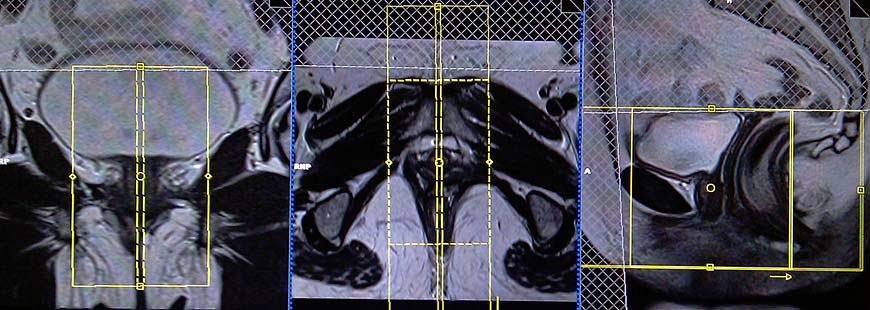

T2 tse fat sat (or stir)coronal oblique 3mm

Plan the coronal slices on the sagittal plane; angle the positioning block parallel to the urethra. Check the positioning block in the other two planes. An appropriate angle must be given in the axial plane (parallel to the right and left ischial tuberosities). The slices must be sufficient to cover the whole urethra from mid symphysis pubis to mid rectum. Adding saturation bands on top and in front of the coronal block will reduce artifacts from arterial pulsation, peristalsis, and breathing.

Parameters

TR 4000-5000 | TE 110 | FLIP 150 | NEX 2 | SLICE 3 MM | MATRIX 224X224 | PHASE R>L | GAP 10% | FAT SAT SPAIR |